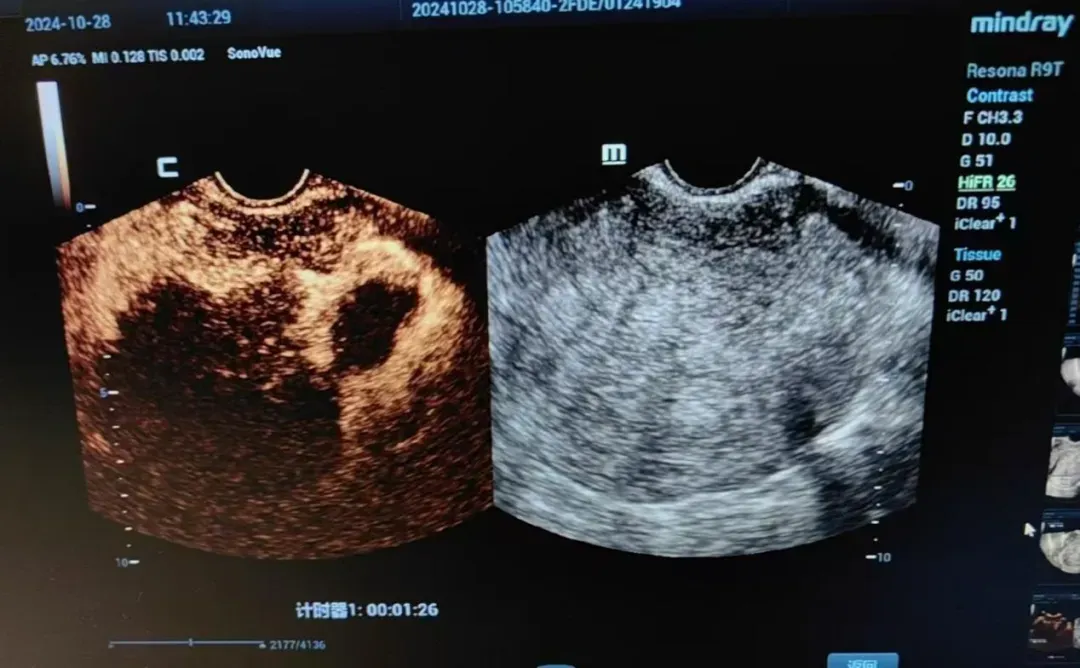

年仅41岁的李女士被子宫腺肌瘤困扰7年多了,有进行性加重的痛经、月经量大、贫血、经常性便秘和尿频等症状。为了治疗这个疾病,李女士四处就医,病程中给予曼月乐环宫腔置入3次(因宫腔过大及月经量过多而脱落),她还用过醋酸亮本瑞林皮下注射,还间断服用过地诺孕素及中药合剂,都没有解决她的痛苦,要完全根治李女士的病症,最彻底的方式是手术切除子宫。然而,对于比较年轻的李女士来说很难接受这种手术方式。经过辗转,李女士来到南京同仁医院妇科门诊找到了万贵平主任。万教授仔细地询问了李女士的病史及其要保留子宫的强烈意愿。由于李女士曾经做过两次子宫下段剖宫产,并且子宫腺肌瘤的病灶位于子宫后壁,最大径线达72mm,经皮及经阴道微波消融极易损伤膀胱直肠及周围组织结构。为了微波消融的精确及安全的进行,万教授为李女士制定了腹腔镜下子宫腺肌瘤微波消融术的手术方案,在腹腔镜及阴道超声引导下行子宫腺肌瘤微波消融。在妇产科、超声科、麻醉科医生的密切配合下,不到1小时就完成了子宫后壁腺肌瘤的消融,术后患者无发热,有轻微的下腹痛。术后5天行超声造影显示腺肌瘤坏死体积达90%,手术非常成功,李女士保住了自己最珍视的子宫,满怀感激的出院了。